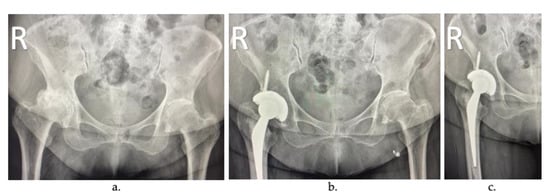

In total joint replacement (TJR), also known as arthroplasty, the diseased or damaged parts of the joint are removed (Figure 2a) and replaced by prostheses or implants (Figure 2b). TJR can be performed on various joints, including the hip, knee, ankle, shoulder, elbow, fingers, and wrist. However, hip and knee prostheses are the most common [].

Figure 2.

Arthroplasty radiographs: (a) patient with severe osteoarthritis in the right hip, (b) joint replacement of the femoral component, and (c) cemented joint replacement.

During TJR, the most common method of fixing the implant is with a load-transfer material’s introduction, typically an acrylic bone cement (ABC) (Figure 2c), introduced into the space between the implant and the joint as a flow-able mixture that eventually hardens over time []. The main advantage of these cemented joint replacements is the reduction in the recovery time of the surgery. Once polymerized, the cement can support a load and offer immediate stability, and it has shown excellent long-term results []. However, if the cement layer is loosened, the surrounding bone can be reabsorbed, and implant failure can eventually occur. Today, acrylic bone cements use is around 90% of total hip replacement (THR) surgeries in developed countries such as the United Kingdom, the Netherlands, and France.